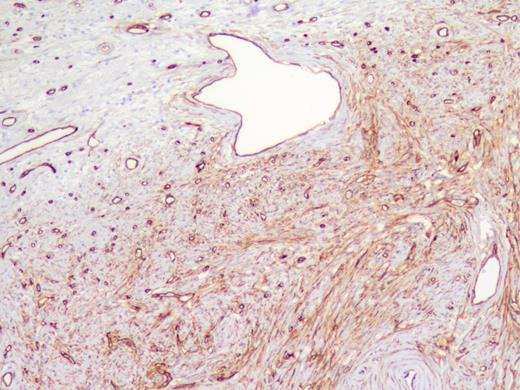

The specimen was a 3.5 ×3 ×3-cm white, firm, well-circumscribed mass located in the head of the pancreas (Fig. 3). The mass was found to be compressing the distal aspect of the main pancreatic duct. All 15 lymph nodes received in the specimen were negative. Histologically, the tumor is well circumscribed from normal pancreatic tissue and composed of spindle cells that in some areas form short ill-defined fascicles and in other areas are randomly arranged in a dense fibrohyaline stroma. A well-developed vascular network was visualized throughout the tumor with vessels of a stag horn appearance with thin hyaline wall and tumor growth around (Figs 4 and 5). No significant mitotic activity or tumor necrosis was noted. Immunostaining was positive for CD34 (Fig. 6) and BLC-2; focally for B-catenin, and focally weak staining for CD99, compatible with fibroblastic origin. The tumor cells were negative for the following cell markers: CD117, CAM5.2, AE1/AE3, EMA, synaptophysin, chromogranin, CD56, PR, SMA, Desmin, S100, MelanA and HMB45. The M1B1 proliferation index was low (<5%). These findings in combination are consistent with a SFT.